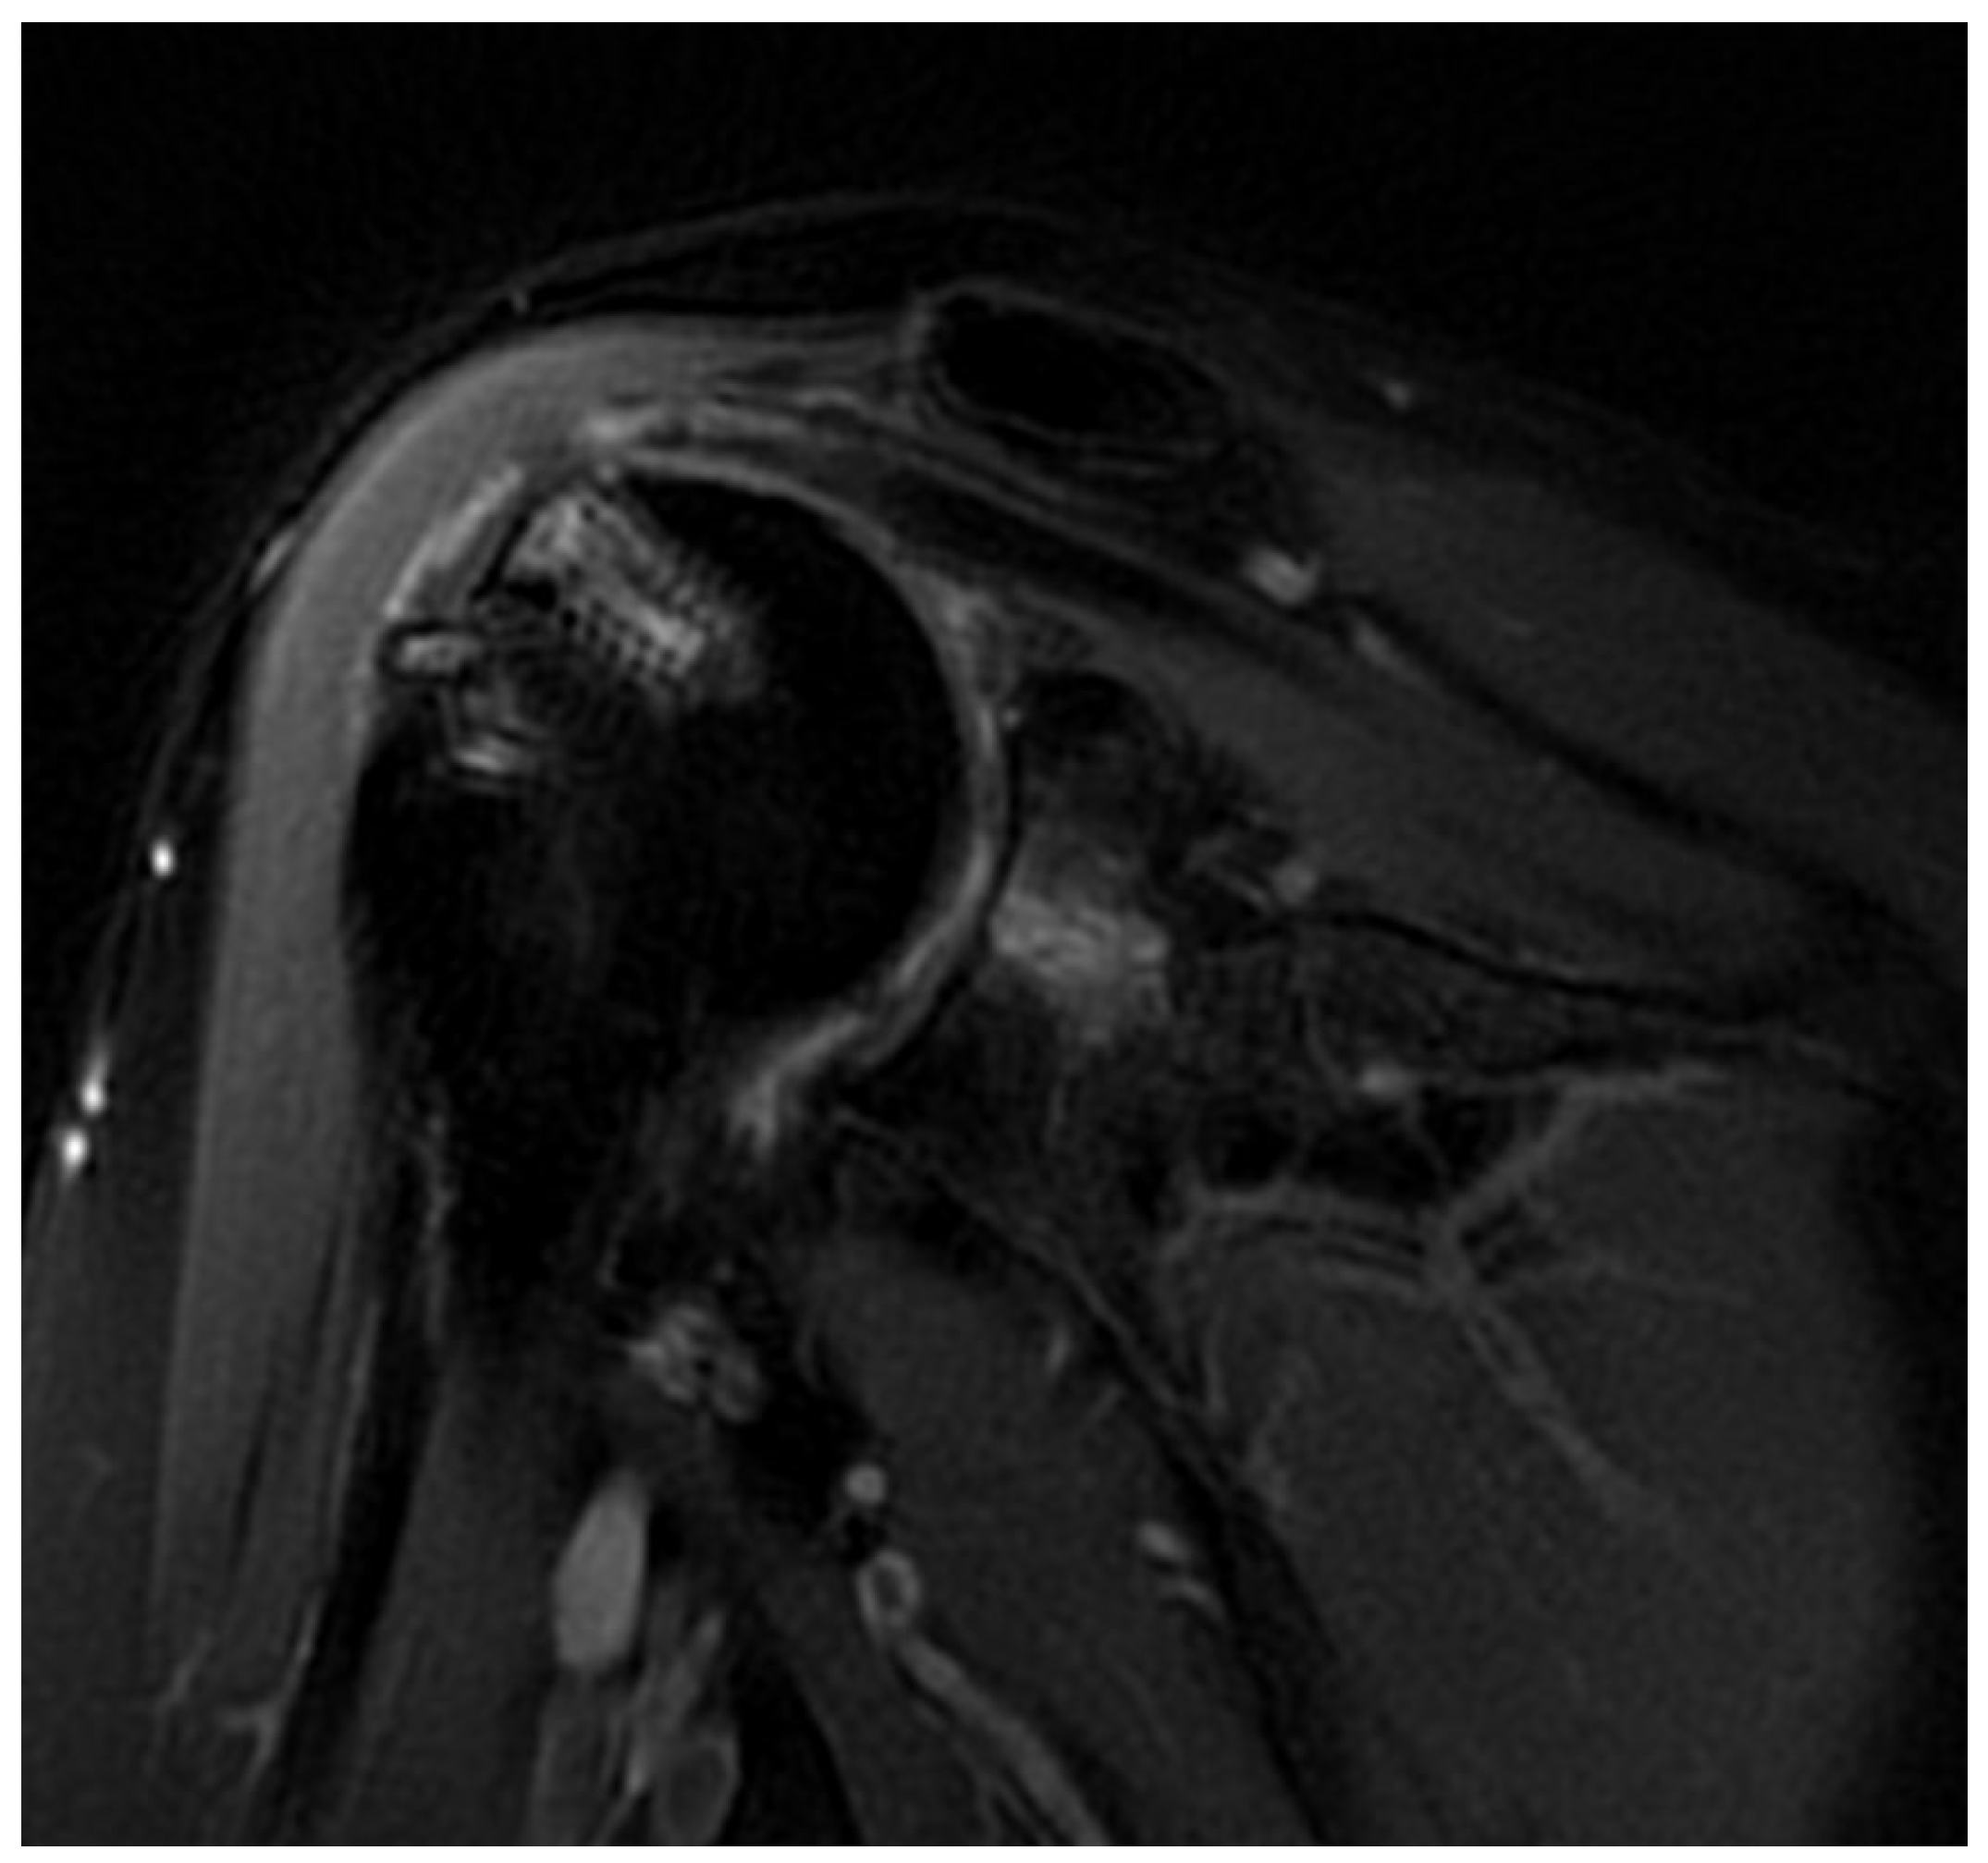

Twenty total patients underwent RCR with DBM. Of the 20, 10 patients demonstrated failure of their repair on post-operative MRI, 5 patients demonstrated an intact repair on the post-operative MRI and 5 did not receive a postoperative MRI given their excellent clinical improvements (Figure 1). The five subjects that did not have a post-operative MRI were considered non-failures.

Figure 1. T2-weighted sagittal MRI of a shoulder following successful healing of a supraspinatus tear with DBM, PRP, and cBMA augmentation.